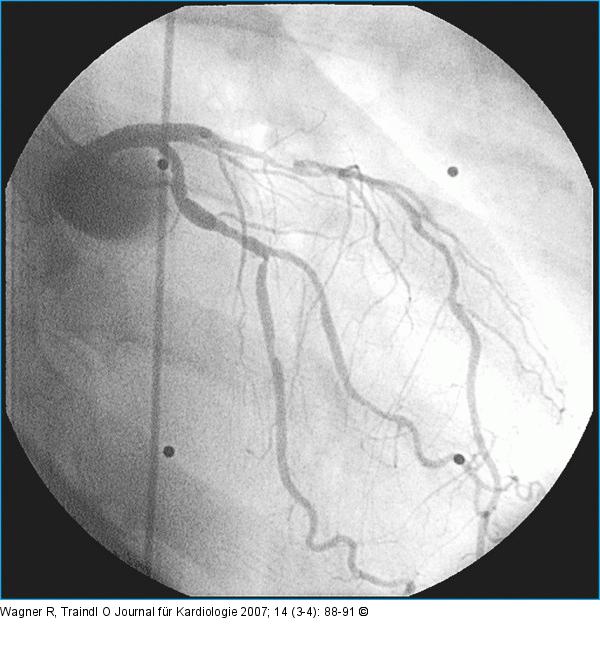

Abbildung 1: LAD-Läsion Proximal hochgradige, mediale langstreckig diffuse LAD-Läsion, RAO |

Proximal hochgradige, mediale langstreckig diffuse LAD-Läsion, RAO |